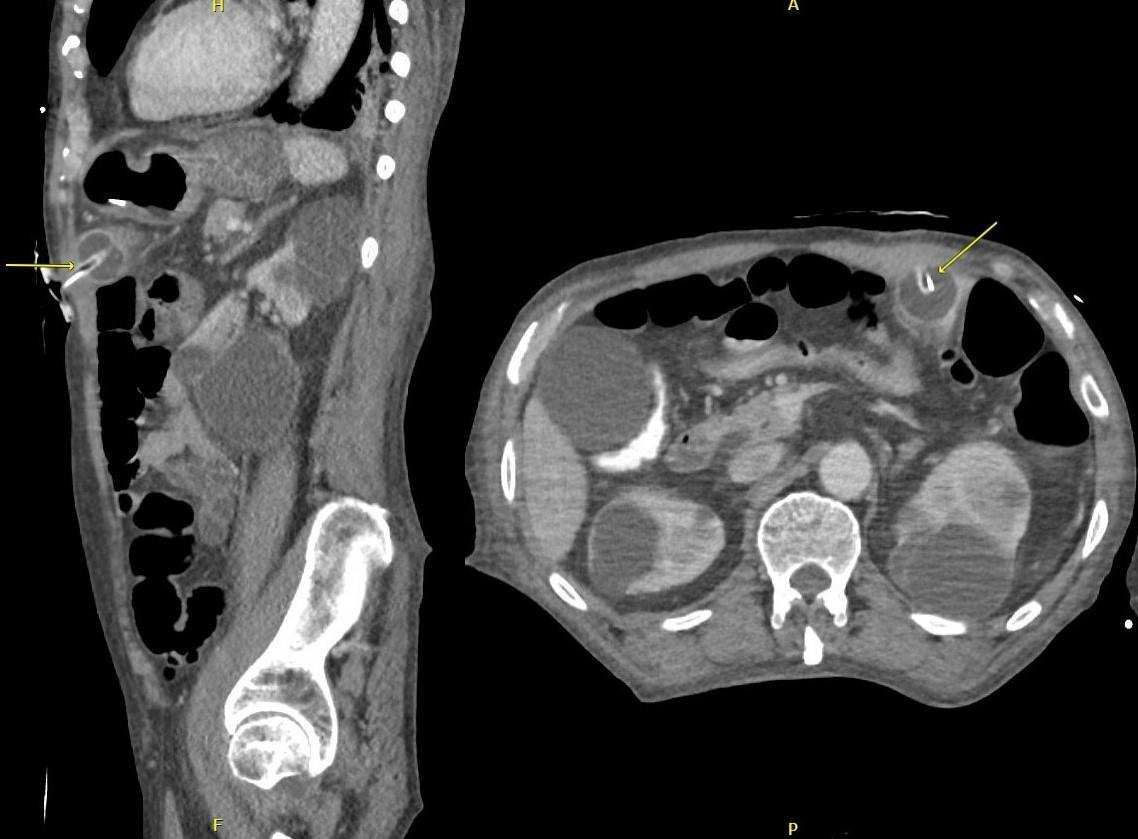

Oninitialevaluation,vitalsignswerenormalexceptfor sinustachycardiaat105beatsperminute.Hewasinmild distresswithmoderatetendernesstopalpationintheleftupper quadrant.Therewasnoguarding,rebound,orrigidity. Laboratoryevaluationshowedawhitebloodcellcountof 21.7 × 103 cellspercubicmillimeter(mm3)(referencerange 4.5 11 × 103 cells/mm3)withaneutrophilpredominanceof 18.9 × 103 cells/mm3 (2 7.8 × 103 cells/mm3)andanelevated bloodureanitrogenat25milligrams(mg)/deciliter(dL) (9–20mg/dL).Thepatient’selectrolytes,liverfunction tests,andserumcreatininewerewithinnormallimits. Acomputedtomography(CT)oftheabdomenandpelviswith intravenouscontrastwasorderedtoassessforbowel obstruction,perforation,andballoonintegrity.TheCT indicatedintraluminalgastricballoonwithanteriorgastricwall perforationwithoutevidenceofintestinalpathology(Image).

GeneralsurgerywasconsultedandobtainedaCT abdomenandpelviswithoralcontrast,whichdirectly showedextravasationintotheperitonealcavity.Thepatient wasemergentlytakentotheoperatingroomforan exploratorylaparotomy,abdominalwashout,removalofthe IGB,andgastricperforationrepair.Hewasstartedon piperacillin/tazobactamand fluconazoleforpurulent peritonitis.Afteranovernightstayinthesurgicalintensive careunit,hewastransferredtothesurgical floorwherehe remainedforthefollowing10days.Onday5,afollow-up uppergastrointestinalserieswithgastrografinwasobtained, andnocontrastextravasationwasnoted.Thepatient’sdiet wasadvanced,andhewasdischargedonpostoperativeday 10withamoxicillin-clavulanatefor10days.Forty-twodays afterdischargethepatientwasnotedtoberecoveringwellon afollowupvisit.